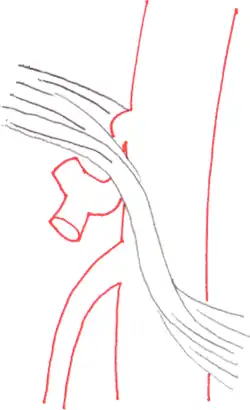

Side views (sagittal plane) of the descending aorta and two of its branches, the celiac trunk and superior mesenteric artery, demonstrate normal and MALS anatomy. Left The median arcuate ligament is normally several millimeters to centimeters superior to the origin of the celiac artery. Right In MALS, the ligament is anterior, rather than superior, to the celiac artery, resulting in compression of the vessel and a characteristic hook-shaped contour.

The median arcuate ligament is a ligament formed at the base of the diaphragm where the left and right diaphragmatic crura join near the 12th thoracic vertebra. This fibrous arch forms the anterior aspect of the aortic hiatus, through which the aorta, thoracic duct, and azygos vein pass. The median arcuate ligament usually comes into contact with the aorta above the branch point of the celiac artery. However, in up to one quarter of normal individuals, the median arcuate ligament passes in front of the celiac artery, compressing the celiac artery and nearby structures such as the celiac ganglia.[2] In some of these individuals, this compression is pathologic. It leads to the median arcuate ligament syndrome.[2]